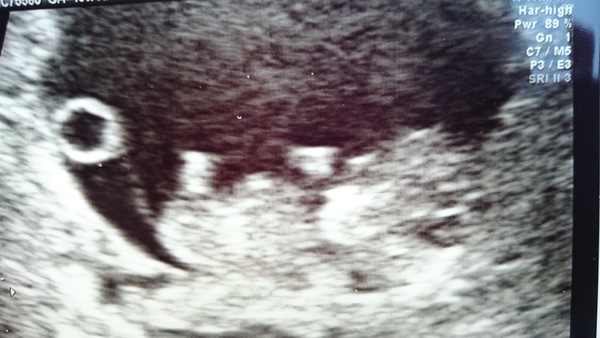

Here is my little wriggler!

The circle at left is the yolk sac and the baby is just over 3cm from head to bottom. Awww Smile